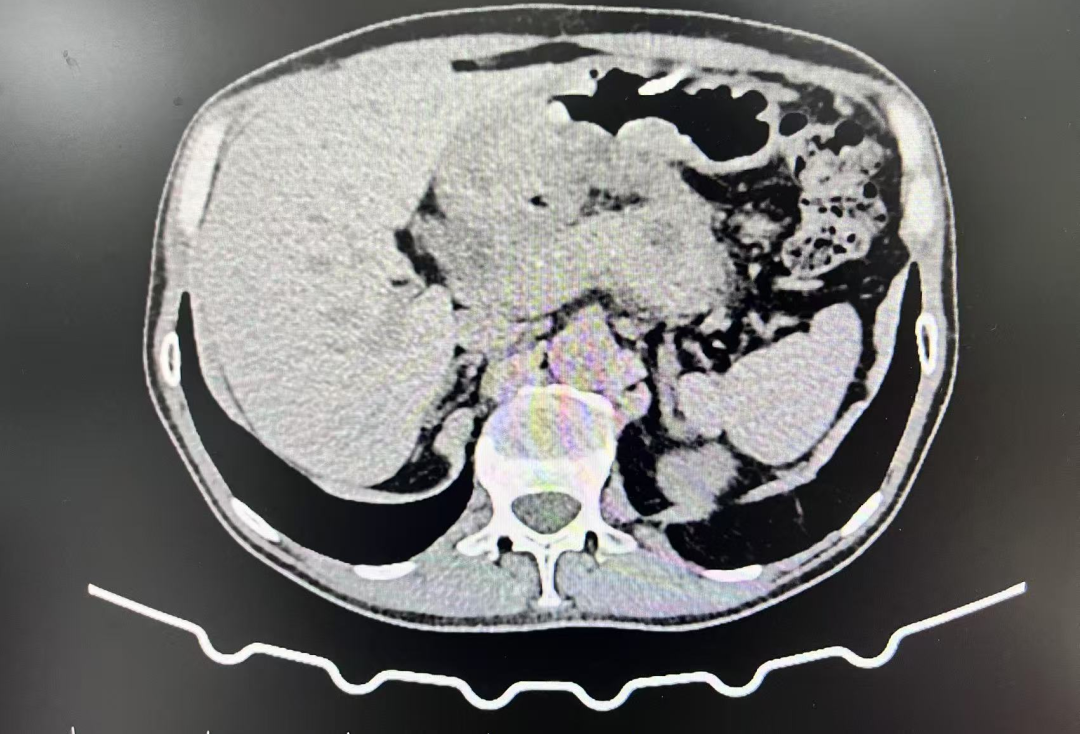

近日,51岁的王叔叔因腹痛呕吐3天入住我院消化内科,经完善相关检查后,磁共振【上腹部MRI平扫】提示:1.胰腺信号异常,多考虑:慢性胰腺炎急性发作。2.胰头颈区囊性病变,多考虑包裹性坏死。3.胰体囊性灶(囊腺瘤可能);【超声胃镜检查】提示:1.慢性胰腺炎,胰管多发结石2.胰头颈部囊性病灶(假性囊肿可能)3.浅表性胃窦炎